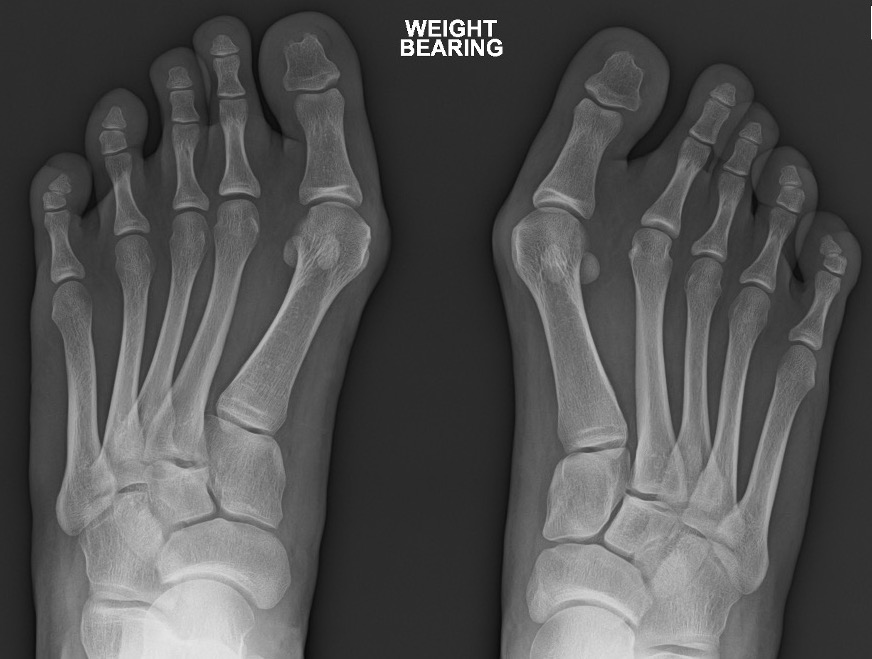

X-ray

Growth plates open

Congruent joint

Increased DMMA

Oblique first TMT joint with metatarsus adductus

Hallux valgus interphalangeus